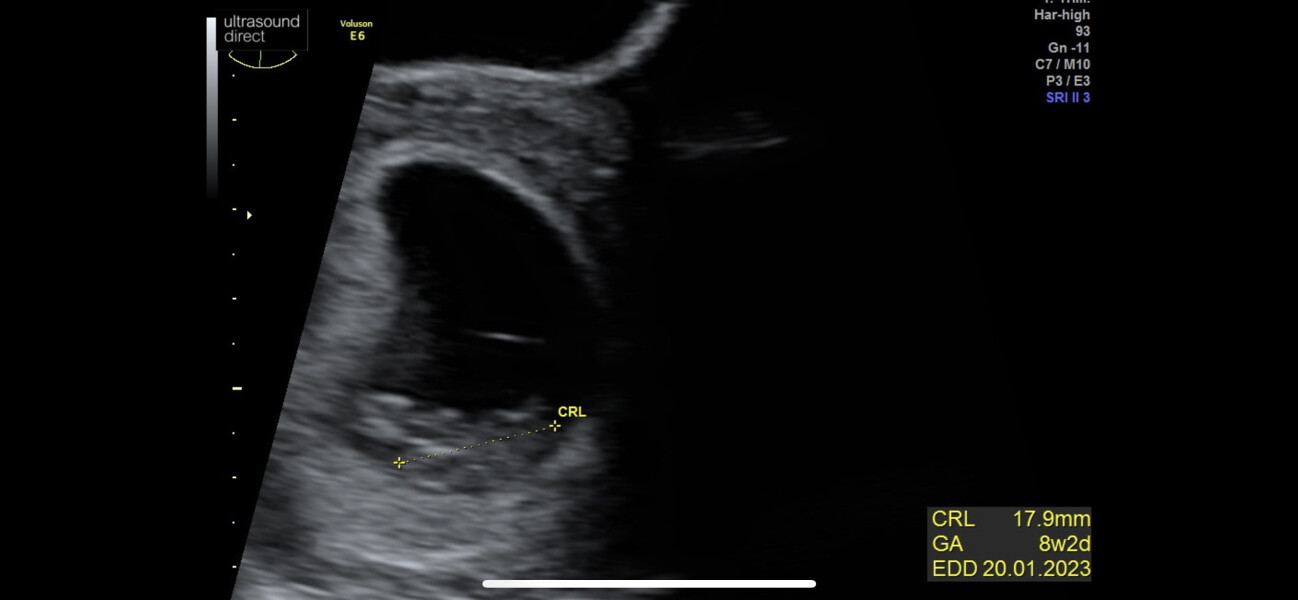

irishgem92 · 12/06/2022 16:28

Good afternoon ladies 💕

Had my scan this morning, my little blob looked great 🥹 blob is measuring at 8+2 and a teeny 17.9mm long with a flicker of a heart beat ❤️

Thanks again for everyone's kind messages 🥰

8 Week Scan Experiences please

OP posts: